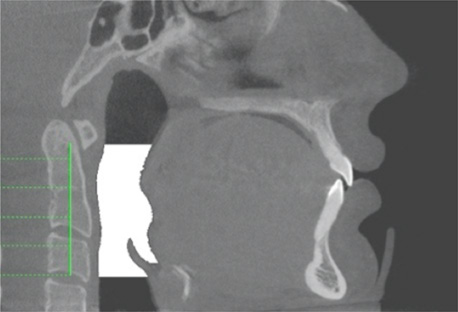

Die Rücklage eines oder beider Kiefer führt immer dazu, dass die oberen Atemwege eingeengt werden.

Bei einer Unterkieferrücklage - ursächlich durch ein unzureichendes Wachstum des Unterkiefers nach vorne - ist meistens der posteroir airway space (PAS), also der hintere Luftbereich im Rachen, reduziert. Oft leiden die Patienten an Übergewicht, was das Schnarchen noch verstärkt. Ein nach hinten fliehendes, kleines Kinn und ein Doppelkinn sind weitere Anzeichen, die in der Profilansicht einfach festgestellt werden können.

Hierbei liegt auch die Zunge und der Zungengrund im gleichen Maße zu weit hinten. Dadurch kann eine Behinderung der hinteren Atemwege vorliegen, wenn beim Schlafen die Muskulatur und auch die Zunge relaxiert und entspannt sind, wobei es zu einer vollständigen Behinderung der Atemwege - einer sogenannten Obstruktion – kommt, was also als OSAS (obstruktives Schlafapnoe-Syndrom) beschrieben wird.

Bei einer Oberkieferrücklage liegt meist das Gaumenzäpfchen zu weit im Rachen. Ebenso bildet der Gaumen den Boden der Nase, sodass Fehlstellungen des Oberkiefers deshalb oft mit einer eingeschränkten Nasenatmung verbunden sind. Betroffene atmen vermehrt durch den Mund und schnarchen aus diesem Grund häufig. Weitere häufige Probleme infolge der Mundatmung sind chronische Mandelentzündungen (Tonsillitis) und – weil die Nase als natürlicher Filter der Atemluft ausfällt – Allergien bis hin zu Asthma.